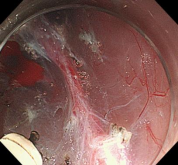

胃窦的腺癌 行ESD治疗

术中见较粗穿支血管,裸化后凝除,最终高效、安全的切除病灶。